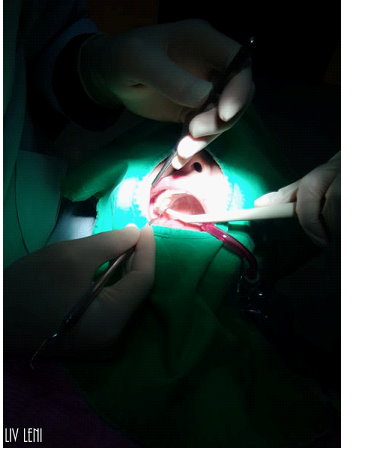

打上麻藥後,開始進行 右邊口腔的牙周刮除術,

雖然看器械好像很可怕,

但因為麻藥的關係,過程中是沒有感覺的,而且相當快速。

(可能也跟病患狀況輕重有關係)

2014.11.12 第二次牙周治療「牙根刮除術」

今天要進行 左側牙周刮除術,

打麻藥就像被蚊子叮一樣(還是我比較不怕痛@@!?)

過程感覺就像有人拿東西在刮牙齒,有摩擦拉扯感。

醫師都會細心的講解概況喔~